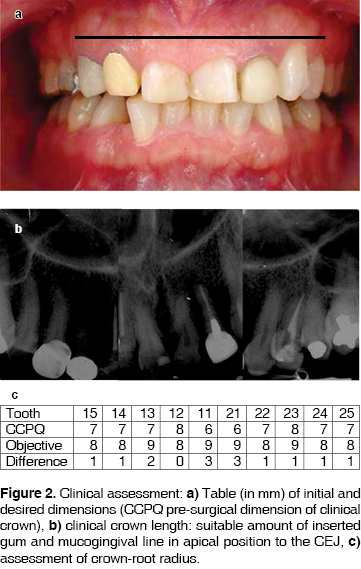

When the zone was defined, incisions were performed with inner bevel and 15C scalpel blade (Figure 3a) on bleeding points. Incisions were performed from the medial aspect of teeth up to their distal aspect. Papillae located between teeth 11-21 and 21-22 were considered within the incision. Intra-groove incisions were then immediately performed, so as to obtain a band of gingival tissue which was then removed with Gracey's® curettes. Clinical assessment of the new gingival margin level was conducted, so as to establish suitable and harmonious dental dimension which could provide targeted aesthetics. Soft tissues were re-contoured until suitable dimensions were reached.

Once the desired height of the gingival margin was determined, a Hopkins periosteal elevator was used to raise a total thickness flap in order to gain access to the alveolar bone. It was observed that alveolar bone level was not uniform in all teeth.

An ostectomy was performed with rotary system with number three carbide round burr, making sure of not touching the roots and preserving suitable festoon. An osteoplasty was also performed in order to provide positive bone architecture (Figure 3b). At this surgical moment the measure from prosthetic margin to new bone crest was taken so as to obtain a 3 mm distance, preserving thus the biological width of the insertion (Figure 3c). Remaining bone attached to root surfaces was removed with Ochsenbein chisels.

Once a suitable distance was determined which would allow recreation of biological thickness and height of clinical crown to facilitate prosthetic rehabilitation, the flap was sutured with 0000 silk.

Upon completion of suturing process, it was observed that the vestibular frenulum was not well placed and did traction the flap. This situation could endanger the long-term stability of the newly created gingival margin. Therefore, it was decided to perform a frenectomy procedure with scalpel and 15c blade. Upon completion of procedure, 0000 suturing silk was used (Figure 3d). Surgical dressings were not placed.